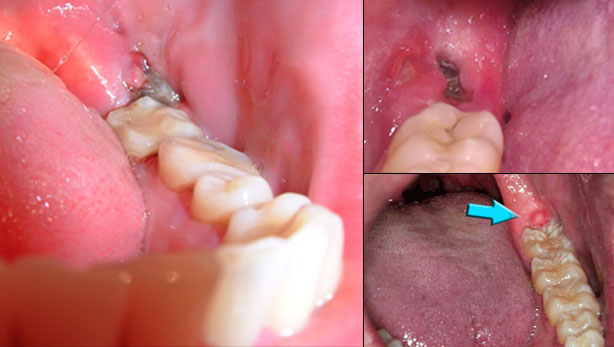

Câu hỏi: Chào bác sĩ Hoàn Mỹ. Mấy hôm nay em bị mọc răng số 8 ở hàm dưới, phần nướu sưng lên rất to làm em không thể há…